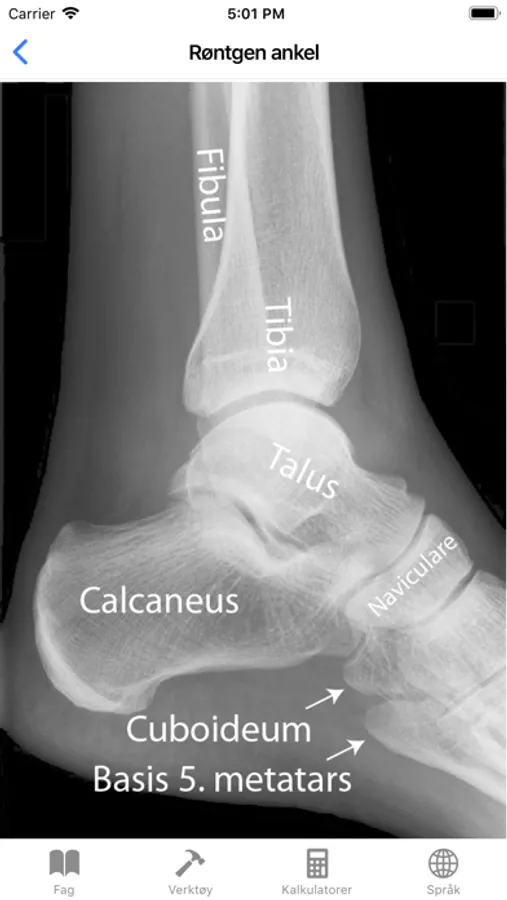

Røntgen ankel